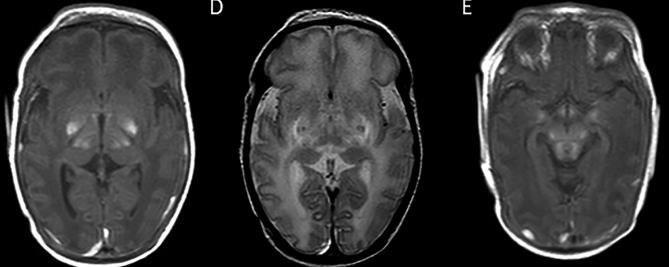

Germinal matrix-intraventricular haemorrhage (GMH-IVH)

Focal infarction

White matter injury

Global injury from hypoxic-ischaemic encephalopathy (HIE)

The study of brain connectivity can produce biomarkers of damage and functional recovery in Cerebral Palsy (CP).

Patients with spastic and dystonic CP have different structural connectivity maps.

Patients with CP show different motor functional connectivity maps, with reduced interthalamic connectivity.